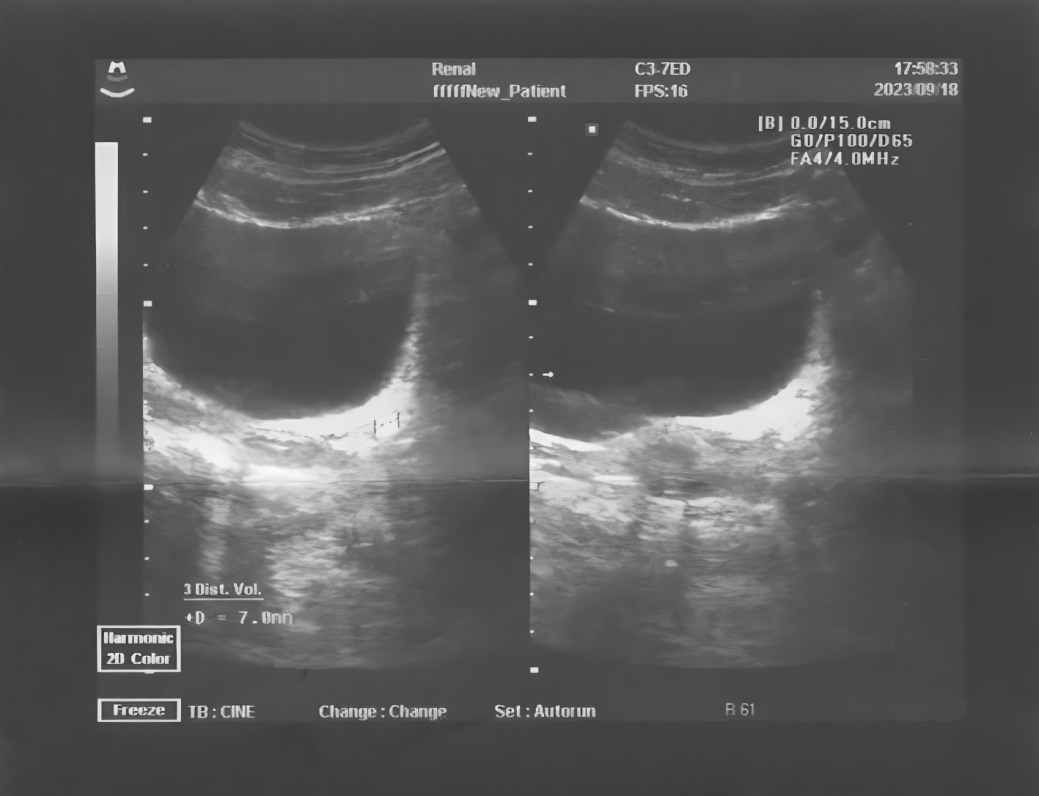

Instrumental studies. Ultrasound examination of the kidneys and bladder dated September 20th, 2023 (Figs. 1 and 2):

- Left kidney: size 10.5 ´ 4.6 cm, normal location, smooth contours, PCS expanded and deformed (pelvis – 1.6 cm, calyx – 0.8 cm), ratio of PCS to parenchyma is normal. Additional signs: a microlith in the upper calyx, triangular shape, 4.2 ´ 2.0 mm with shadowing; a microlith in the lower calyx – 2.5 ´ 3 mm with shadowing. The lower third of ureter on the left expanded to 0.4 cm with the presence of internal structures in the form of a hyperechoic formation sized 7.0 ´ 4 mm with shadowing at 2.2 cm from the ureteral orifice. Discharge from the orifice on the left is slowed and weakened.

Fig. 2. Patient G. Ultrasound of the bladder from September 20th, 2023. Hyperechoic formation in the lower third of the ureter on the left

Conclusion: Ultrasound-signs of concretion in the lower third of the ureter on the left, concretions of both kidneys, urostasis on the left.